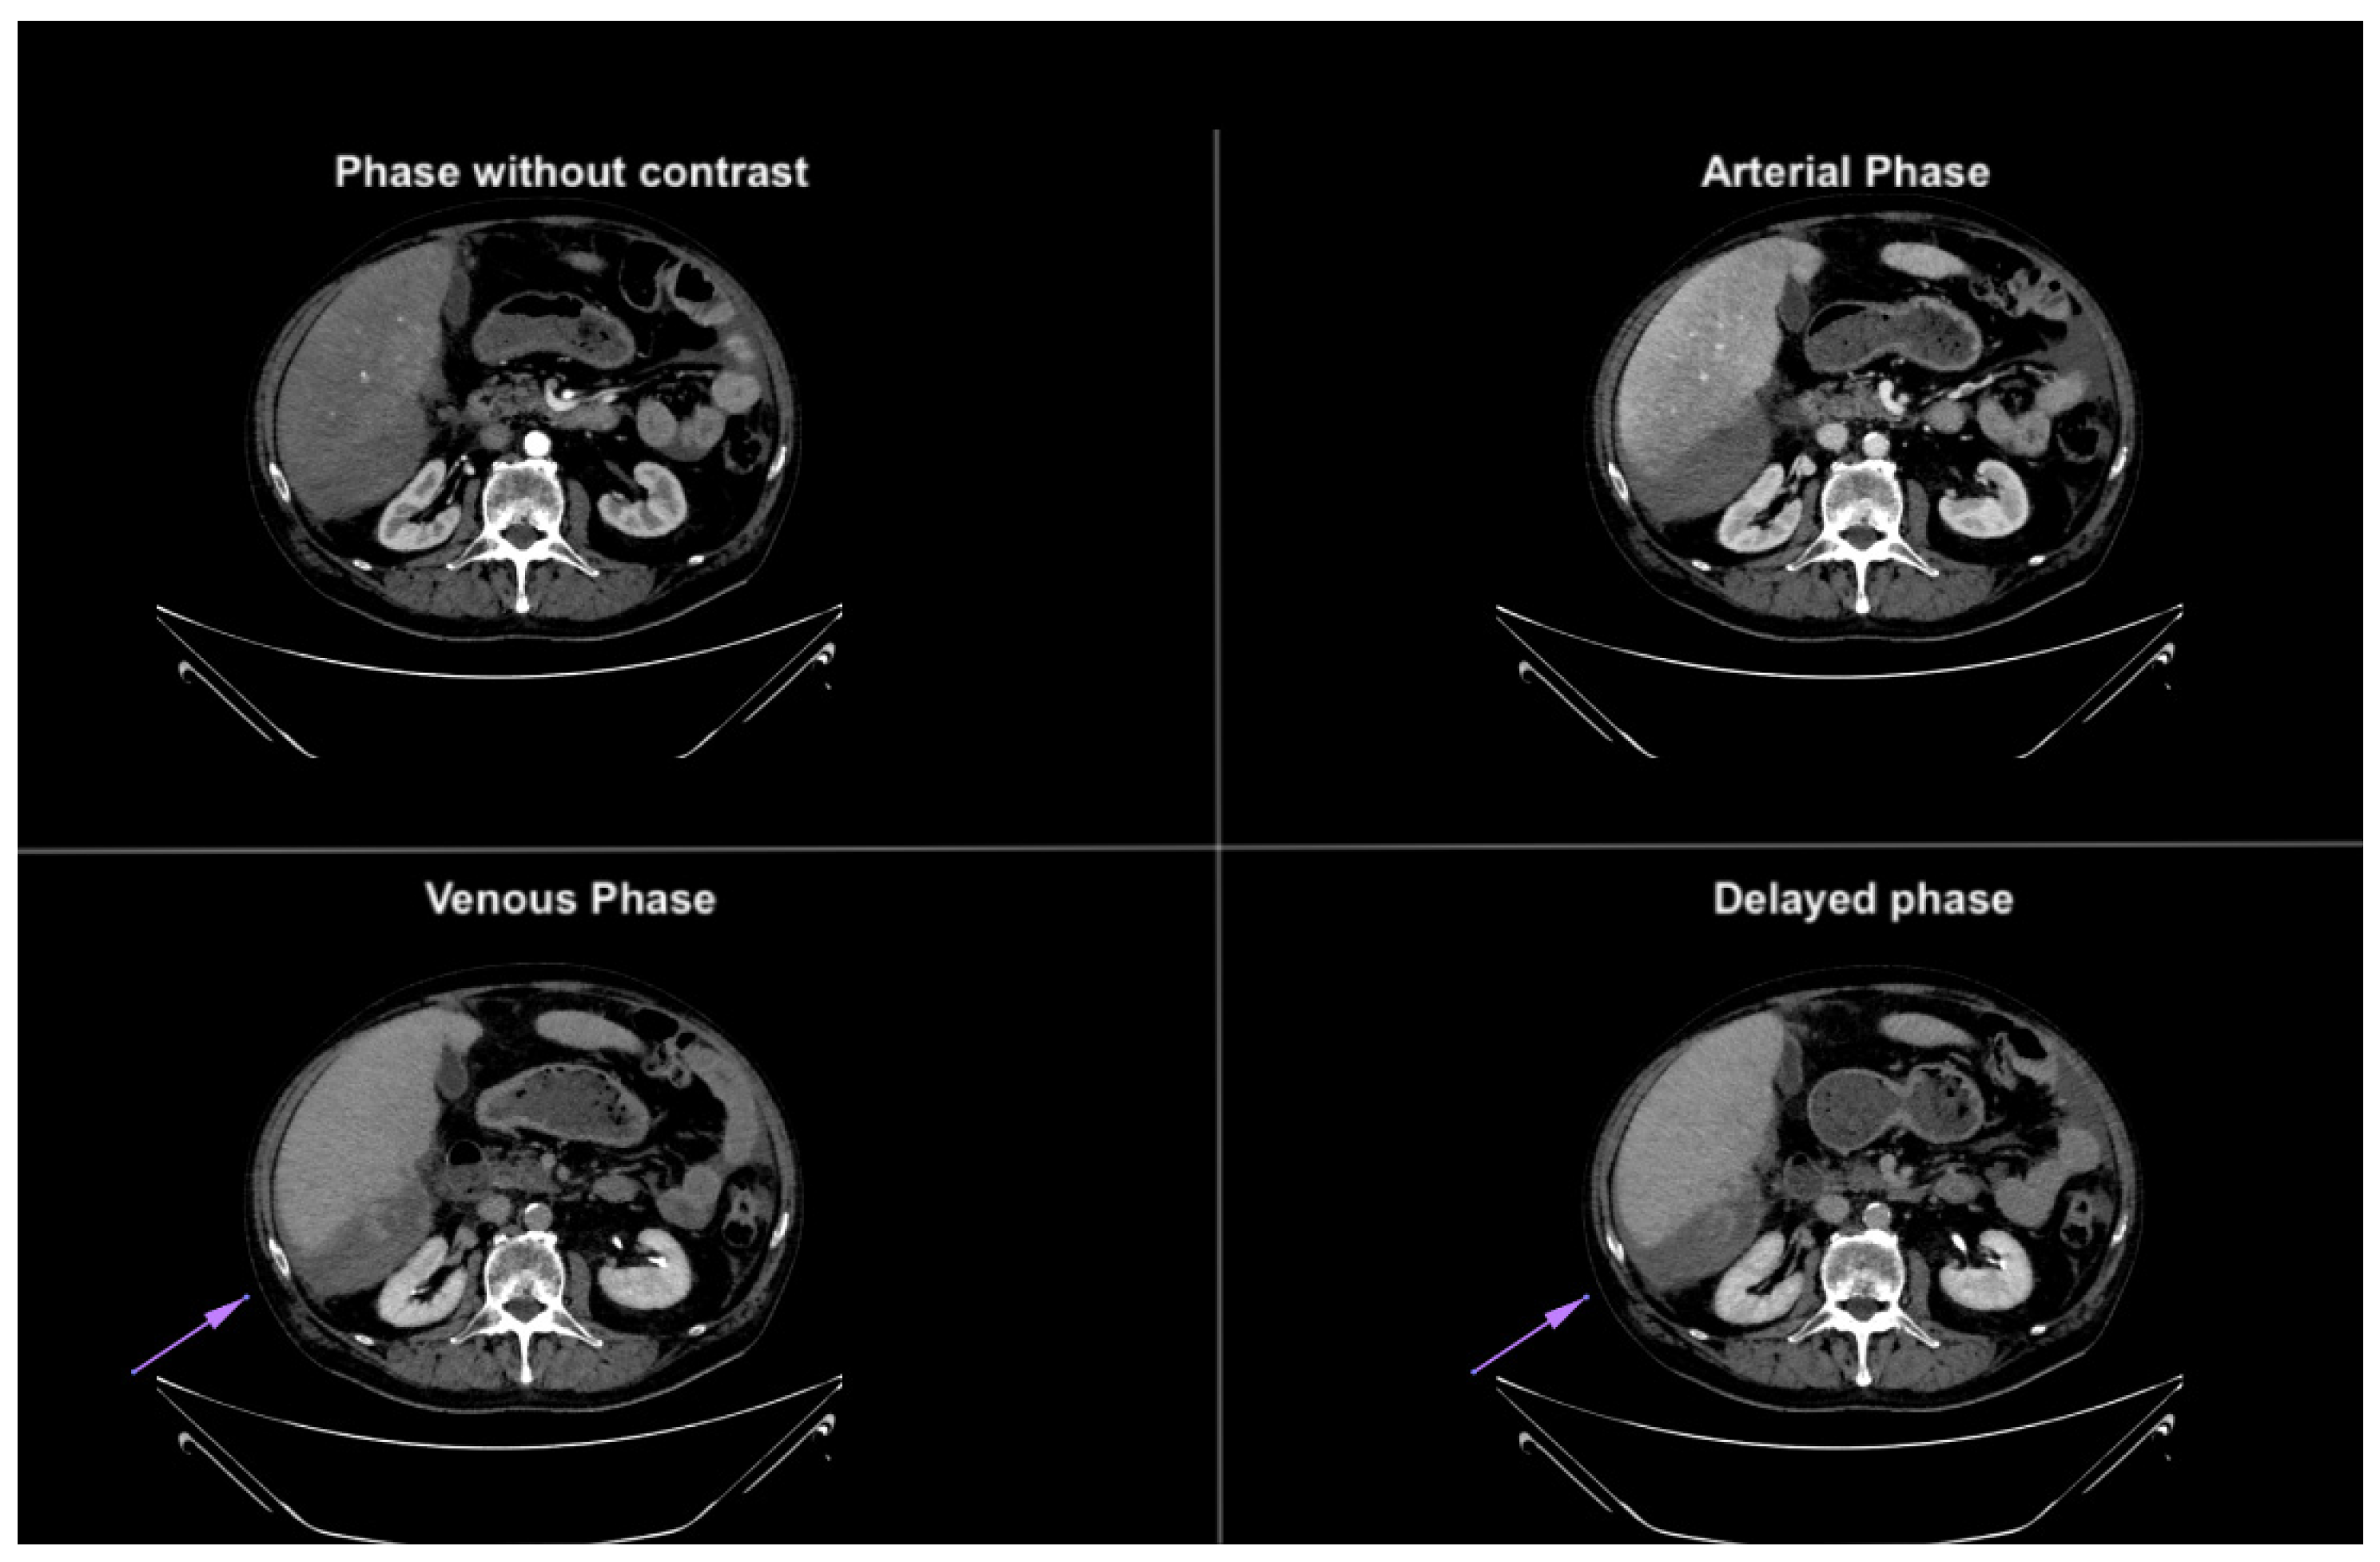

Figure 4. Axial CT images in different phases, highlighting extravasation of contrast medium within the subhepatic fluid collection. The extravasation becomes more prominent in the last phases, confirming the presence of active bleeding. The purple arrow demonstrates blood extravasation in the collection during the venous and delayed phases of the study, not visible in the baseline and arterial phases.